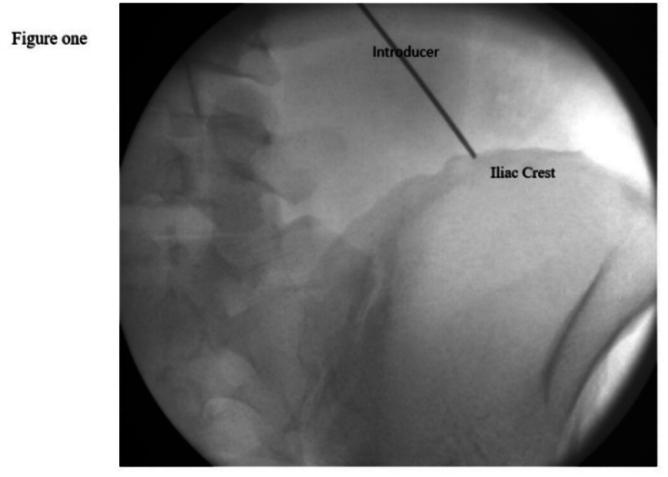

This case series aims to evaluate the effectiveness of the Micro Lead - SPRINT Peripheral Nerve Stimulation (PNS) System, (Cleveland, Ohio, USA) for treating cluneal neuralgia, utilizing both fluoroscopic and ultrasound guidance for accurate nerve localization.

A retrospective review was conducted on six nonconsecutive patients who underwent Micro Lead - SPRINT Peripheral Nerve Stimulation (PNS) System, (Cleveland, Ohio, USA) implantation for cluneal nerve entrapment at MetroHealth System between August 2021 and January 2024. Patient selection focused on individuals with cluneal neuralgia refractory to conservative treatments. Data collection included demographics, pain characteristics, opioid usage, and follow-up evaluations at 30, 60, 90 days, and 2 years post-procedure. Outcomes were assessed using the Numerical Rating Scale (NRS) for pain. Dividing the NRS score by the maximum score (10) and multiplying by 100 expresses pain intensity as a percentage.